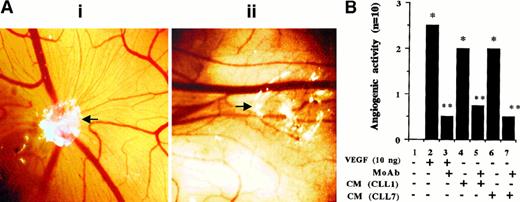

VEGF produced by CLL cells enhances angiogenesis. To test whether CLL-cell–secreted VEGF affects in vivo angiogenesis, the CAM assay was used with angiogenesis by rhVEGF 121 as a positive control. Results were assessed visually (Figure6A) and measured semiquantitatively (Figure 6B), as described in “Materials and methods.” The rhVEGF 121 induced a strong angiogenic response that was neutralized by an anti-hVEGF neutralizing antibody. CLL-cell–derived CM induced moderate angiogenesis that was also prevented by the neutralizing anti-hVEGF antibody. This indicates that CLL-cell–derived CM does have angiogenic activity and that VEGF contained in these supernatants is the major angiogenic factor.

(A) Representative angiogenic response and its inhibition by a blocking anti-hVEGF mAb. The white area represents the site of application of filters containing either CM (collected from the PMA-stimulated cells) alone (i) or the same CM preincubated with anti-hVEGF MoAb for 2 hours at RT (ii). Microvessels radiating from the site of sample application in (i) are not formed in the presence of the blocking mAb (ii). (Original magnification, × 8.) (B) The semiquantitative data obtained by using rhVEGF and CM collected from PMA-stimulated cells from 2 patients. The grading of the angiogenic response is described in “Materials and methods.” *P < .05 vs control andP < .05 vs sample without the neutralizing antibody (Mann-Whitney U test). Each bar represents the score of 10 CAM used in 2 separate assays with similar results.